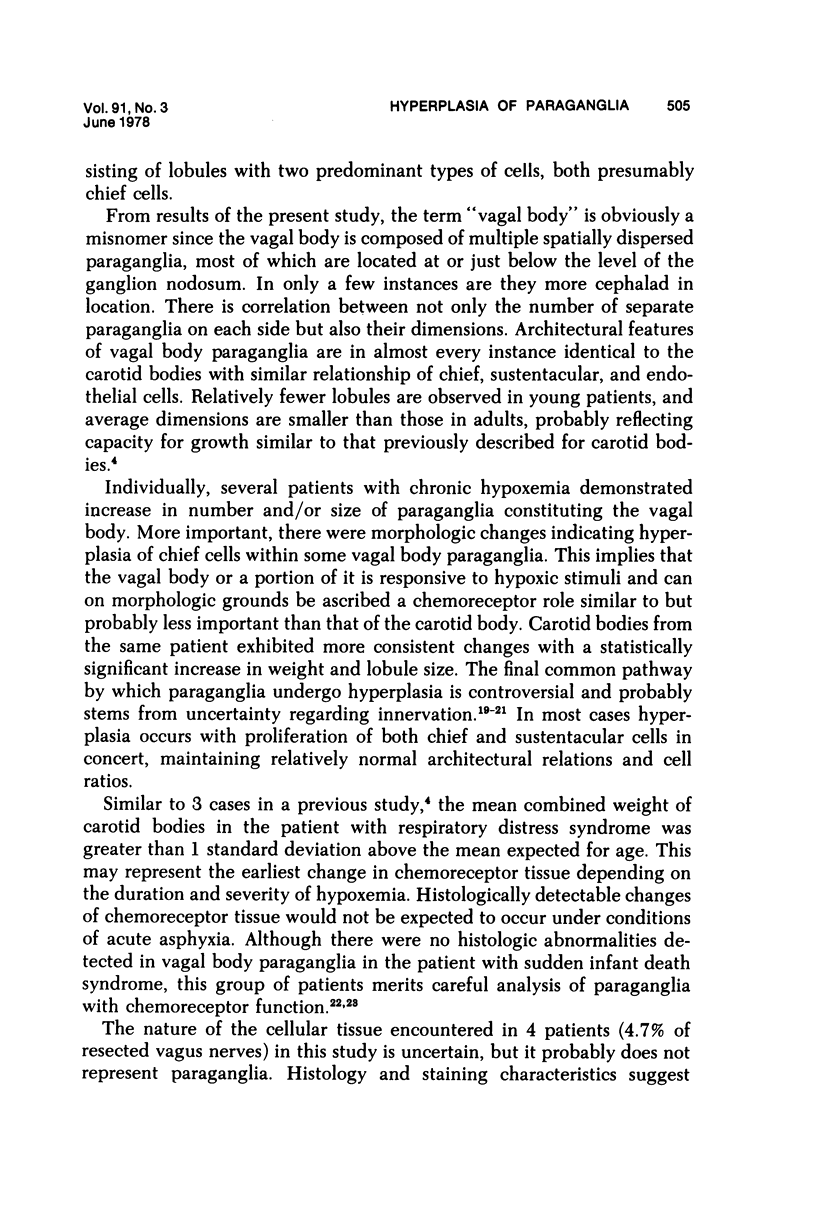

Vagal and carotid body paraganglia were obtained from 43 randomly selected autopsies performed at the National Naval Medical Center. In each case, tissue from both sides was step sectioned and comparatively studied. The mean combined weight of carotid bodies in 37 control patients was 25.9 mg. There was good correlation between size and number of separate paraganglia comprising the vagal body (seven left, six right). Lobules were closely related to the ganglion nodosum and were actually within it in three instances. Tissue resembling parathyroid was encountered within 4 of the 86 resected vagus nerves. Lymphocytic infiltration occurred in carotid and vagal body paraganglia of 28% and 16% of patients, respectively. There was Schwann cell proliferatation in carotid body lobules of 2 patients; in another patient, talc emboli were present. The mean combined weight of carotid bodies in 6 patients with chronic hypoxemia was 47.6 mg, significantly greater than in the control group; in each case, lobules were enlarged. Chief cell hyperplasia occurred in vagal body paraganglia of 2 patients; in two other patients, lobules were large with equal proliferation of constituent cells. These morphologic findings indicate that in patients with chronic hypoxemia some vagal body paraganglia can be ascribed a chemoreceptor role similar to but probably less important than that of the carotid body.